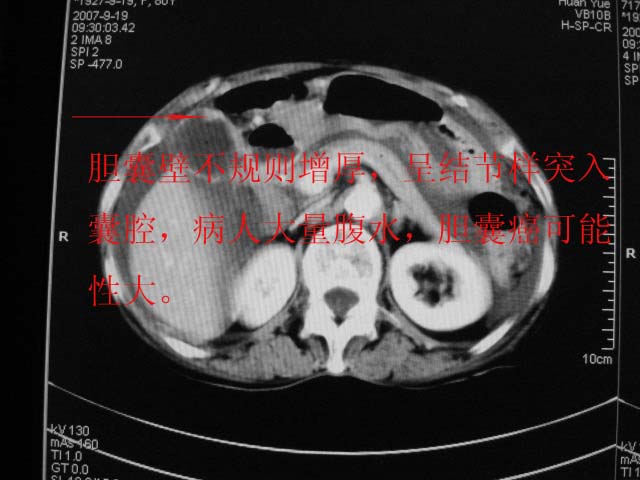

以下是引用默契在2007-9-20 17:29:00的发言:[br][br] [br] 考虑:1、胆囊占位性病变(以癌可能性大);[br] 2、中量腹水。 [br] [br]

以下是引用zjzjr在2007-9-20 19:15:00的发言:[br]慢性胆囊炎伴炎性息肉可能性大.腹水.